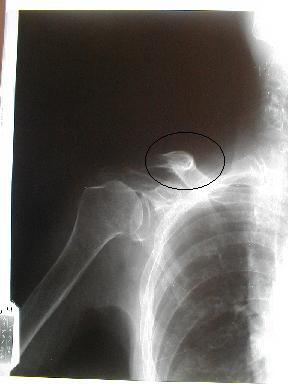

10月28日整復固定x-p

整復固定は、症例2を参照

受傷者が高齢で、なおかつ固定を嫌い早期〔30日間)に除去を願った為変形治癒となった。しかし、上腕挙上も可能で、日常生活動作には何ら支障はない。